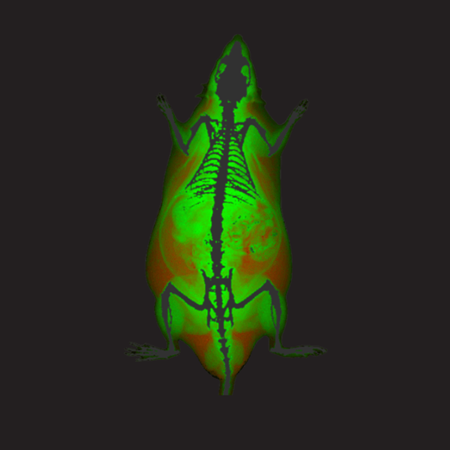

The iNSiGHT technology employs dual energy X-rays to provide highly accurate and repeatable body composition assessments. The system categorizes each pixel into one of three compartments: fat mass, non-bone/lean mass, or bone mineral content, and provides measurements such as bone mineral density, bone mineral content, bone area, tissue area, fat tissue percentage and weight, lean tissue percentage and weight, and total weight in grams.

The X-ray attenuated image, bone mineral density map, and color map are produced in a single scan (25 seconds).

The iNSiGHT system measures changes in fat and lean mass over time to assess disease progression or regression and body composition assessments in response to a treatment program. The colorimetric image distinguishes visceral and subcutaneous fat using regions of interest, which could be useful in further understanding these diseases.

The iNSiGHT system can evaluate changes in body composition parameters following hypoxia exposure. The colorimetric image allows for distinguishing visceral and subcutaneous fat using regions of interest, which may help understand the metabolic effects of such exposures. In this case, hypoxia exposure reduces the amount of fat in mice.

Color Image - Rat. Image Credit: Scintica Instrumentation Inc

Bone Mineral Density Image - Rat. Image Credit: Scintica Instrumentation Inc